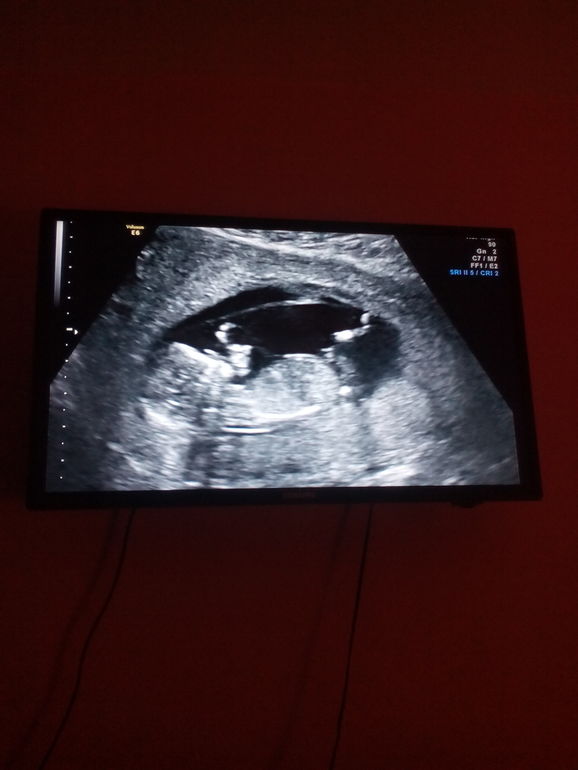

Дождалась скрининг!!!!

Наконец-то познакомились с моим вторым счастьем!!!!

ктр уже 68 мм)))

все параметры в норме,соответствуют сроку!!!! Помахал нам ручкой!! Врач сказала что пока похож на мальчика))) Егорка очень просит брааатика) посмотрим как оно дальше будет)